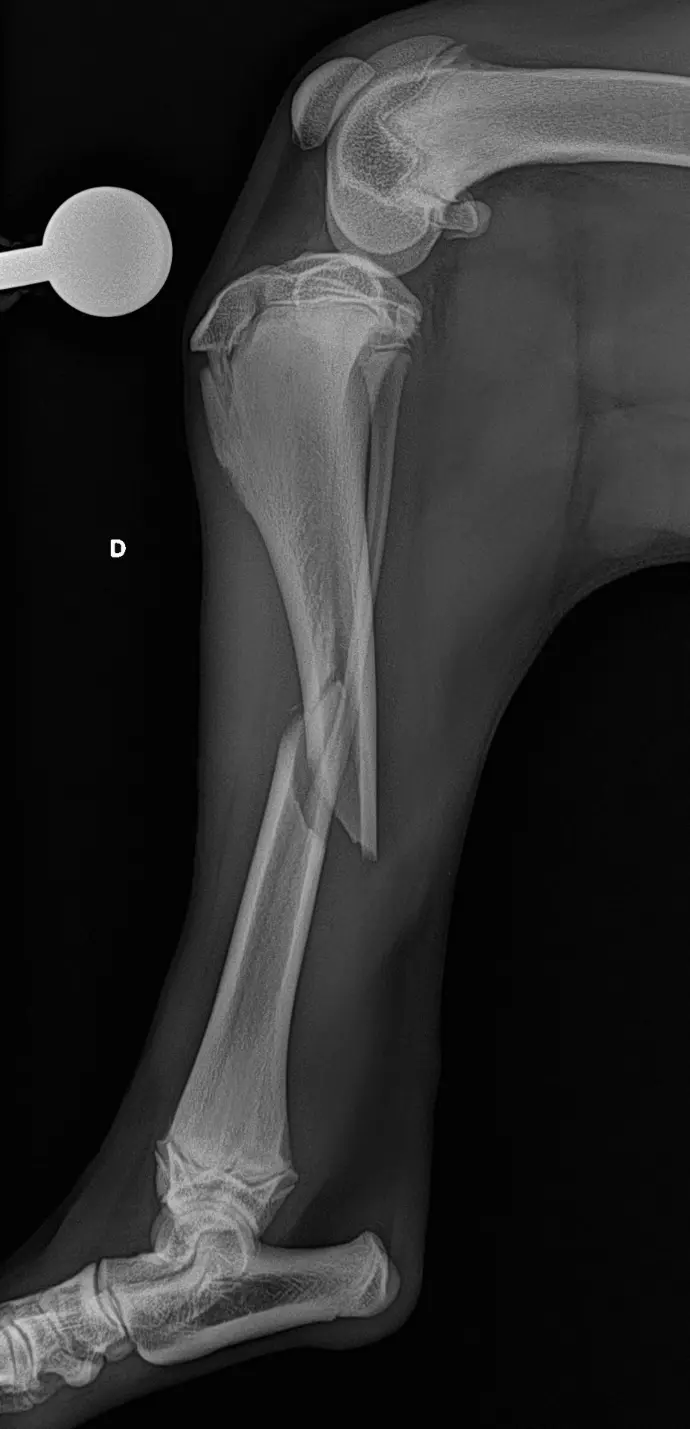

Fracture

- Repos strict pendant 4 à 6 semaines : garder votre animal en cage.

- Pas de saut ni de jeux, courtes sorties en laisse uniquement pour les besoins.

- Ne pas laisser votre animal lécher le pansement ou les sutures, maintenir la collerette jusqu’au retrait des points

- Les pansements peuvent se décoller et tomber dans les prochains jours, ils ne doivent pas être renouvelés.

- Retrait des points dans 12-14 jours chez votre vétérinaire traitant.

- Contrôle radiographique dans 4 à 6 semaines (et au besoin dans 3 mois selon la cicatrisation osseuse).